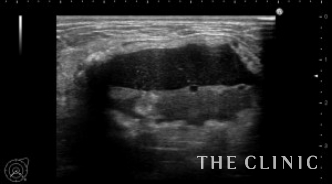

そして今日は、先日大きな石灰化したしこりを摘出、1ヵ月後のチェックに来院された方をご紹介します。

しこりが破れ、周囲に炎症を繰り返していました。

乳輪切開でしこりを摘出します。

ボールの様に大きなしこりがなくなりました。